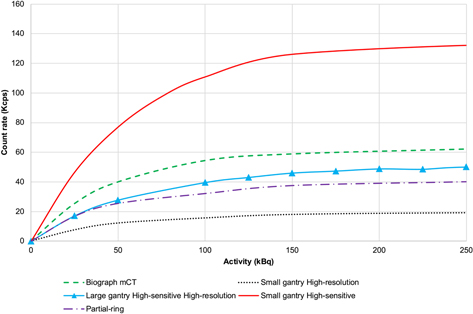

Figure 4 depicts the plots of prompt, true, random, and scatter counts for the different configurations. Figure 5 shows the NECR carve for the different configurations, supporting the results obtained for the sensitivity.

Figure 4. Plots of count rates showing: (a) prompts, (b) trues, (c) randoms, (d) scatter for the simulated configurations of PET scanners compared with the Biograph mCT.

Standard image High-resolution imageFigure 5. NECR performance for the simulated configurations of the Active-PET scanner compared to the simulated mCT PET scanner.

Download figure:

Standard image High-resolution imageThe reconstructed images of the Hoffman 3D brain phantom for the different configurations are illustrated in figure 6. The configuration with a large gantry (high-sensitivity and high-resolution detector modules) showed better image quality providing the highest anatomical details preservation relative to the Biograph mCT. As an example, the Caudate and Putamen regions are more distinguishable from each other and other regions. The scanner with a small gantry and high-resolution detector modules shows better image quality compared to the one with high-sensitivity detector modules, while it may lead to underestimation of radiotracer uptake (the red arrow in the occipital lobe).